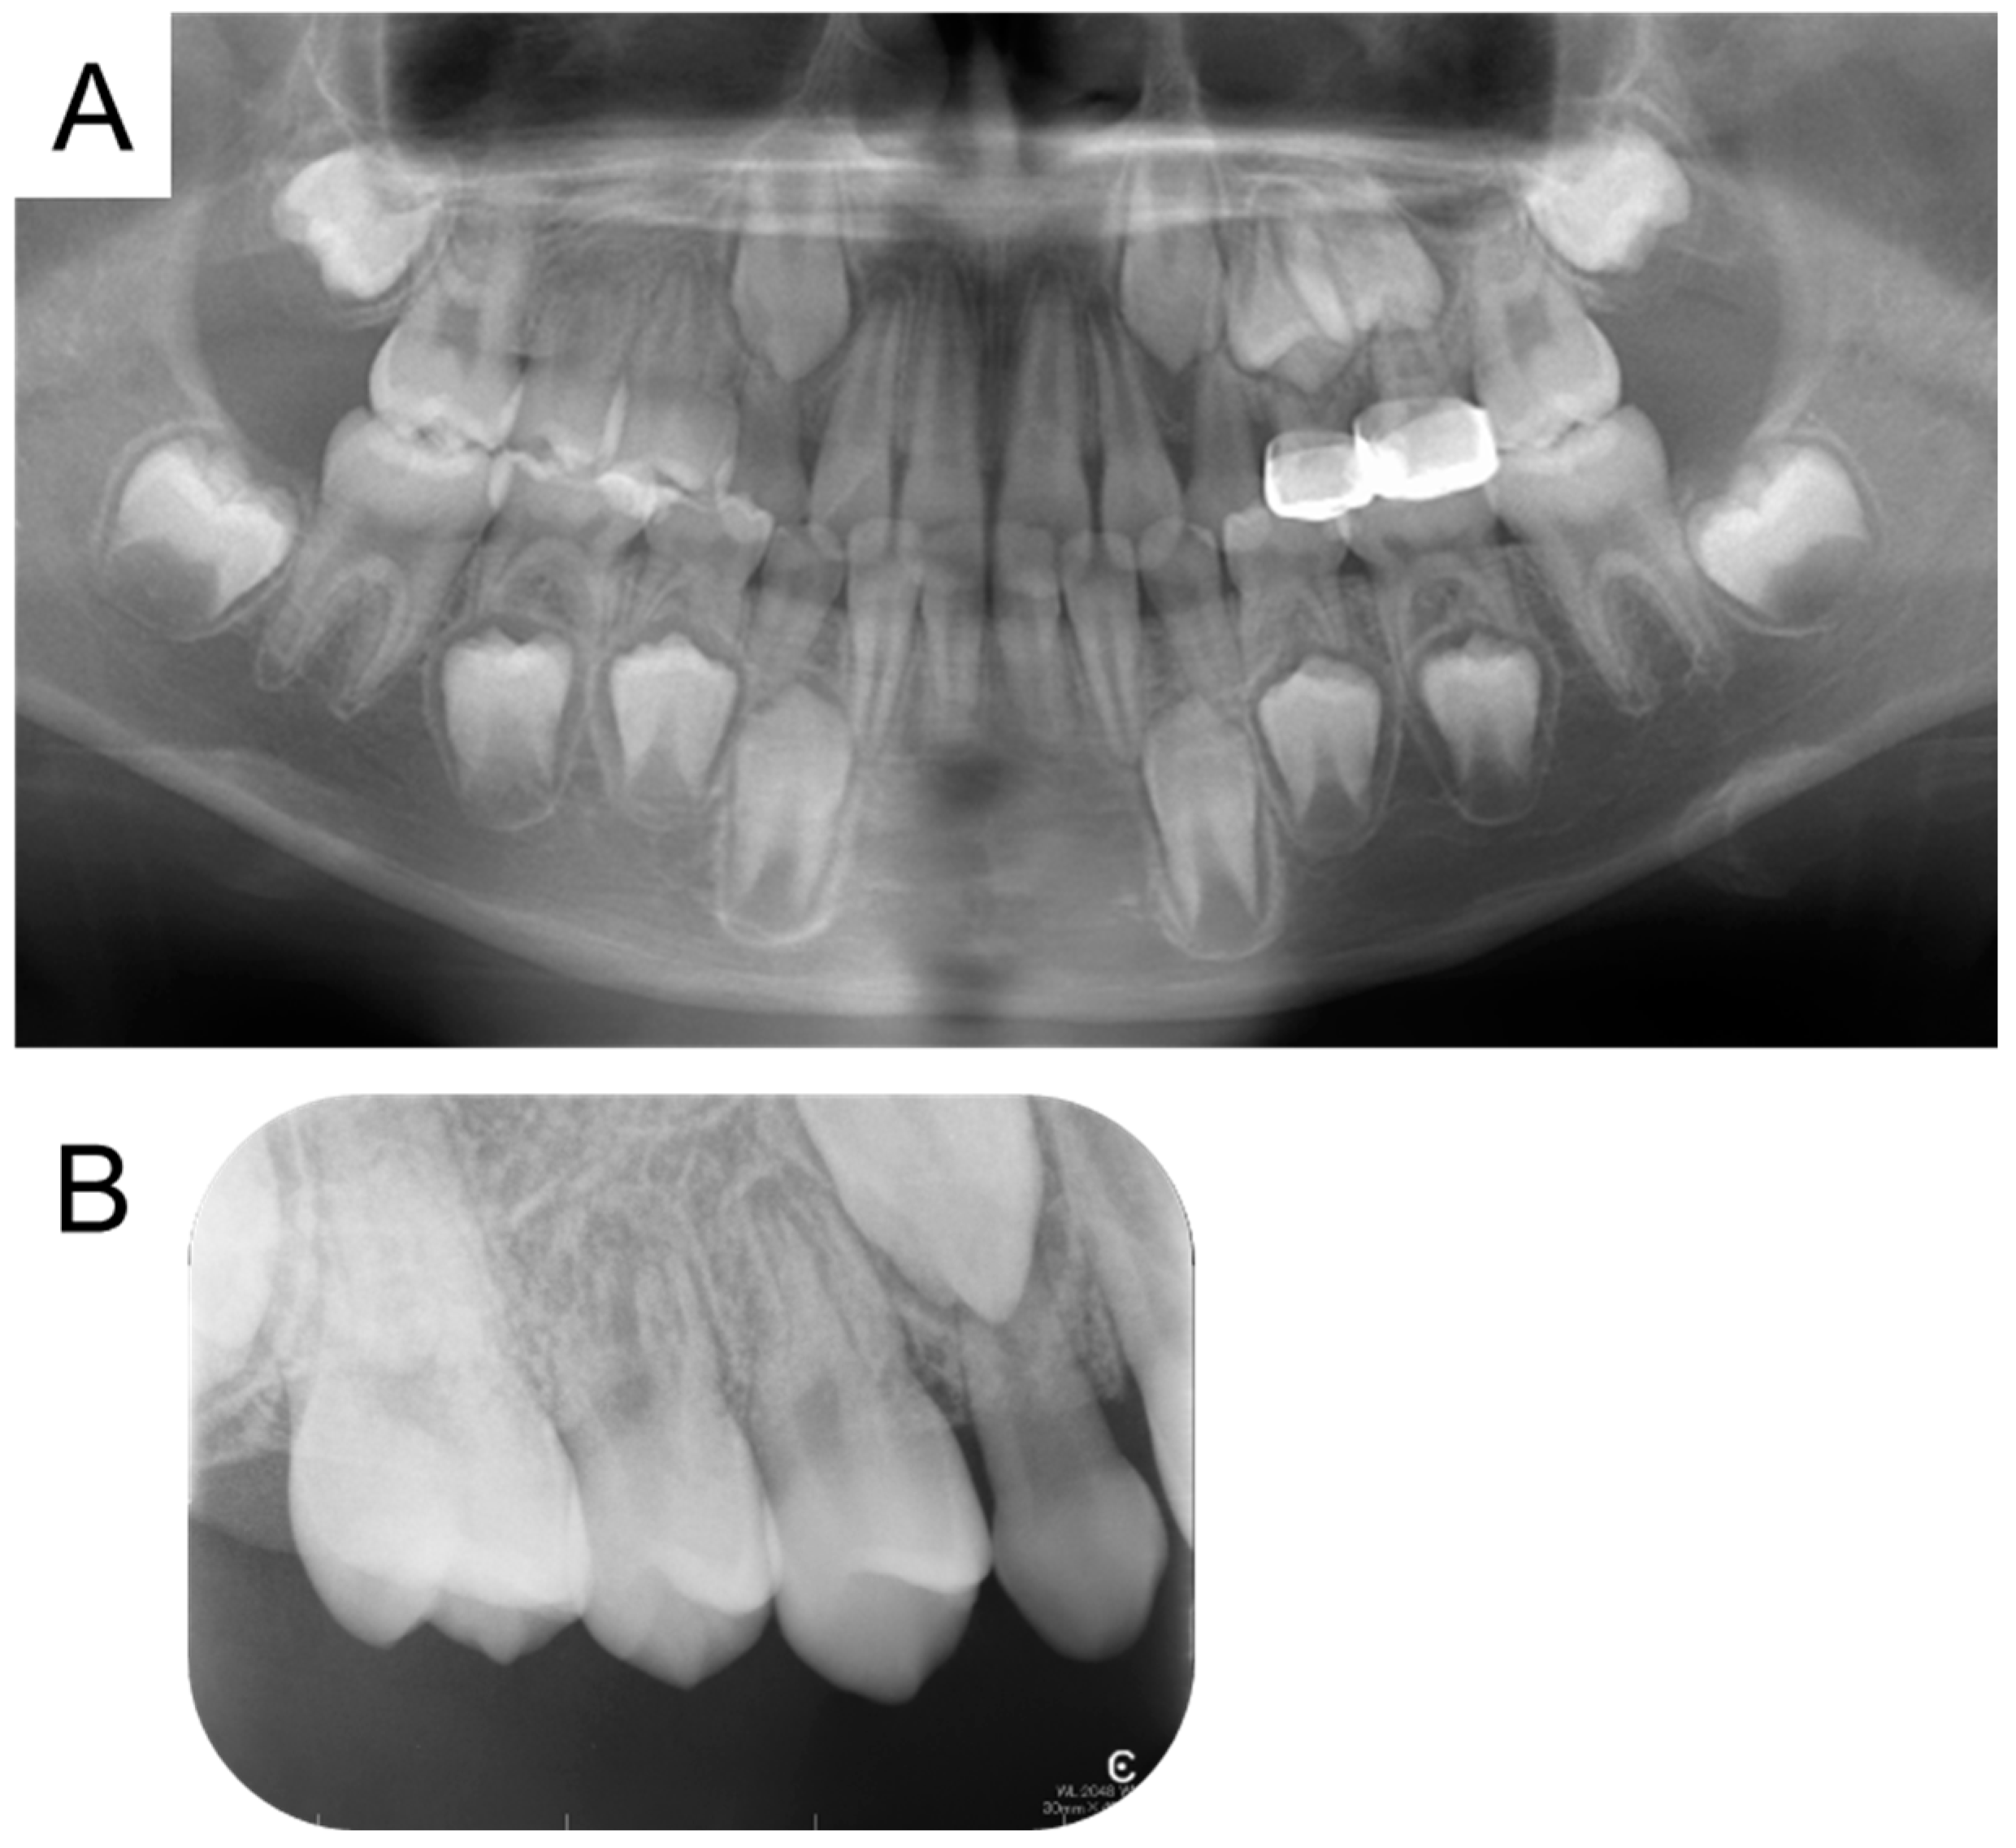

| Present case | #55 | Mesio-buccal canal | Reamer | 17 months | Enamel hypoplasia |